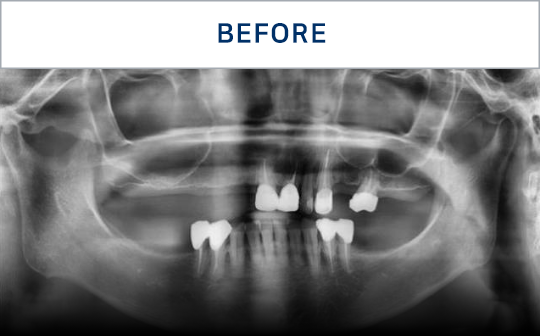

전후가 명확한 결과, 그 결과가

곧 신길플란트치과의 신뢰입니다.

불편함 없이 웃고, 걱정 없이 드실 수 있도록 임플란트로 일상의 편안함을 되찾아드리겠습니다.